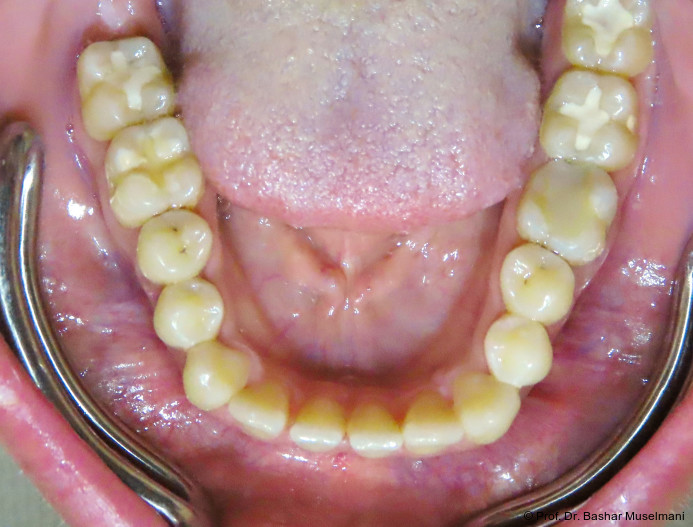

Die Abbildungen 1 bis 3 zeigen die initiale klinische und radiologische Ausgangssituation.

Apparative Versorgung

Die Behandlung erfolgte mittels einer festsitzenden Multibracketapparatur unter Verwendung passiver selbstligierender Brackets (Damon Ultima System) im Ober- und Unterkiefer.